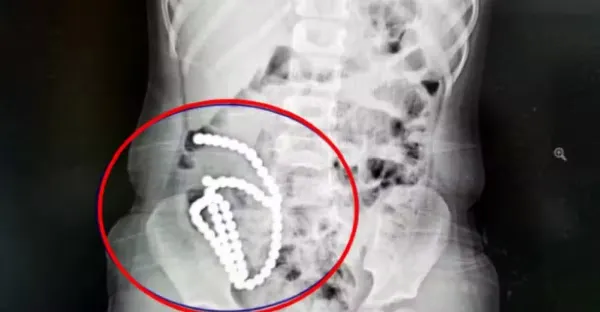

4歲女童照X光驚見「肚裡一串白珠珠」,真相揭曉竟是哥哥在玩!母親崩潰證實,醫生無奈嘆息:恐怕一輩子都毀了

4歲妹照X光驚見「肚子整串白珠珠」 媽證實哥哥在玩!醫嘆:一輩子毀了.